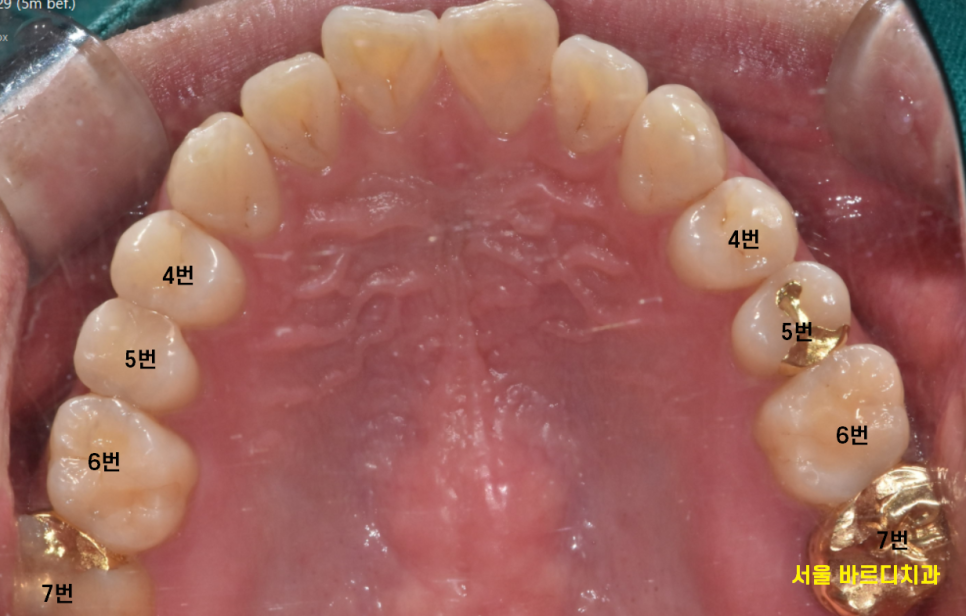

교합도 잘 안맞는게 보이시죠?

치아가 움직이면서

닿던 부위도 안닿고

해당 치아로는

음식을 제대로 씹기 어려우셨을 겁니다.